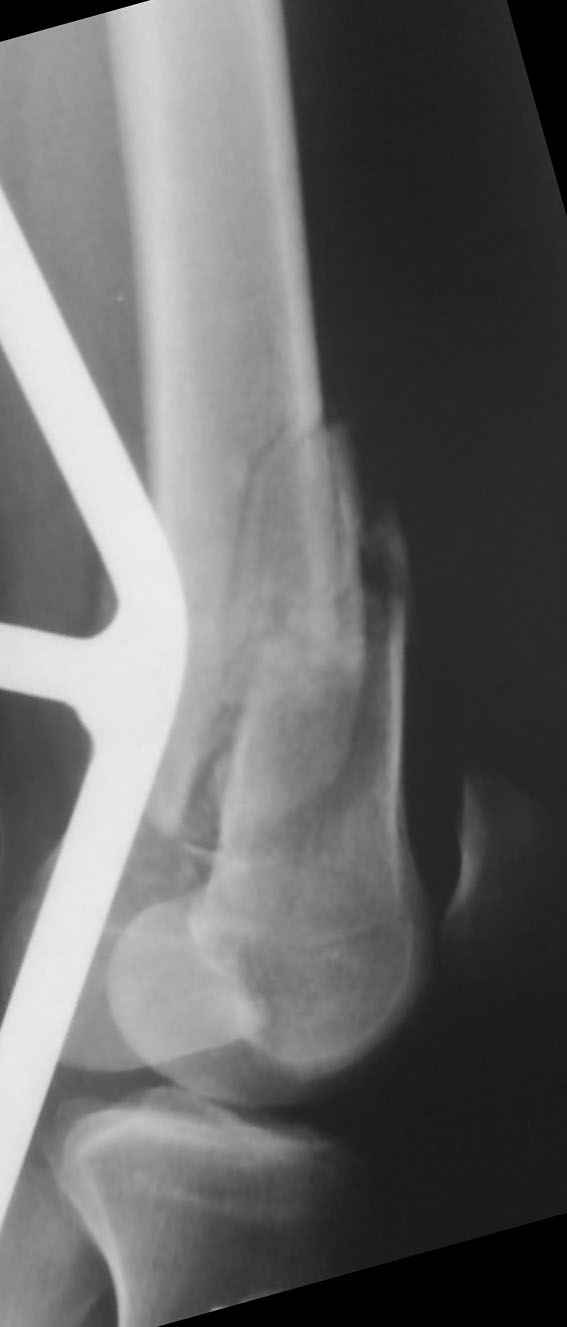

Привет из Нижнего Новгорода! К нам поступил пациент 25 лет с закрытыми переломами обеих бедренных костей, прошел месяц после травмы. Слева - внутрисуставной перелом, поэтому выбор здесь очевиден, открытая репозиция, стабильная фиксация, скорее всего LCP DF, а справа - мнения учёных, как говорится, разошлись. Лично я, как лечащий врач, за закрытый интрамедуллярный остеосинтез DFN. Со мной согласна половина коллектива, другая - за интрамедуллярный остеосинтез (DFN,UFN) но с открытой реопозицией, поскольку при закрытой методике все осколки останутся где-то сбоку, получится дефект и вдруг не срастется!Философский вопрос: что лучше - красивая рентгенограмма или сохранение кровоснабжения? Очень важно мнение коллег! Смирнов Алексей

Приветствую всех коллег!!Во первых слева хотелось бы видеть четкую боковую проекцию а лучше КТ. По р-мам есть сомнения насчет повреждения суставной поверхности. При подобных переломах даже внутрисуставных без смещения хорошие результаты показал закрытый ретроградный остеосинтез универсальным бедренным стержнем Деост.Кстати при внутрисуставном переломе возможно применение вместо винтов стягивающих болтов!!(См. метод.Деост).При переломе справа также стержень Деост. Однако без открытия Вам не удастся устранить интерпозицию, только промучаетесь!Из минимального разреза удалите интерпозициб и фиксируйте стержнем. Причем универсальный стежень Деост позволяет фиксировать дистально минимум на трех уровнях!